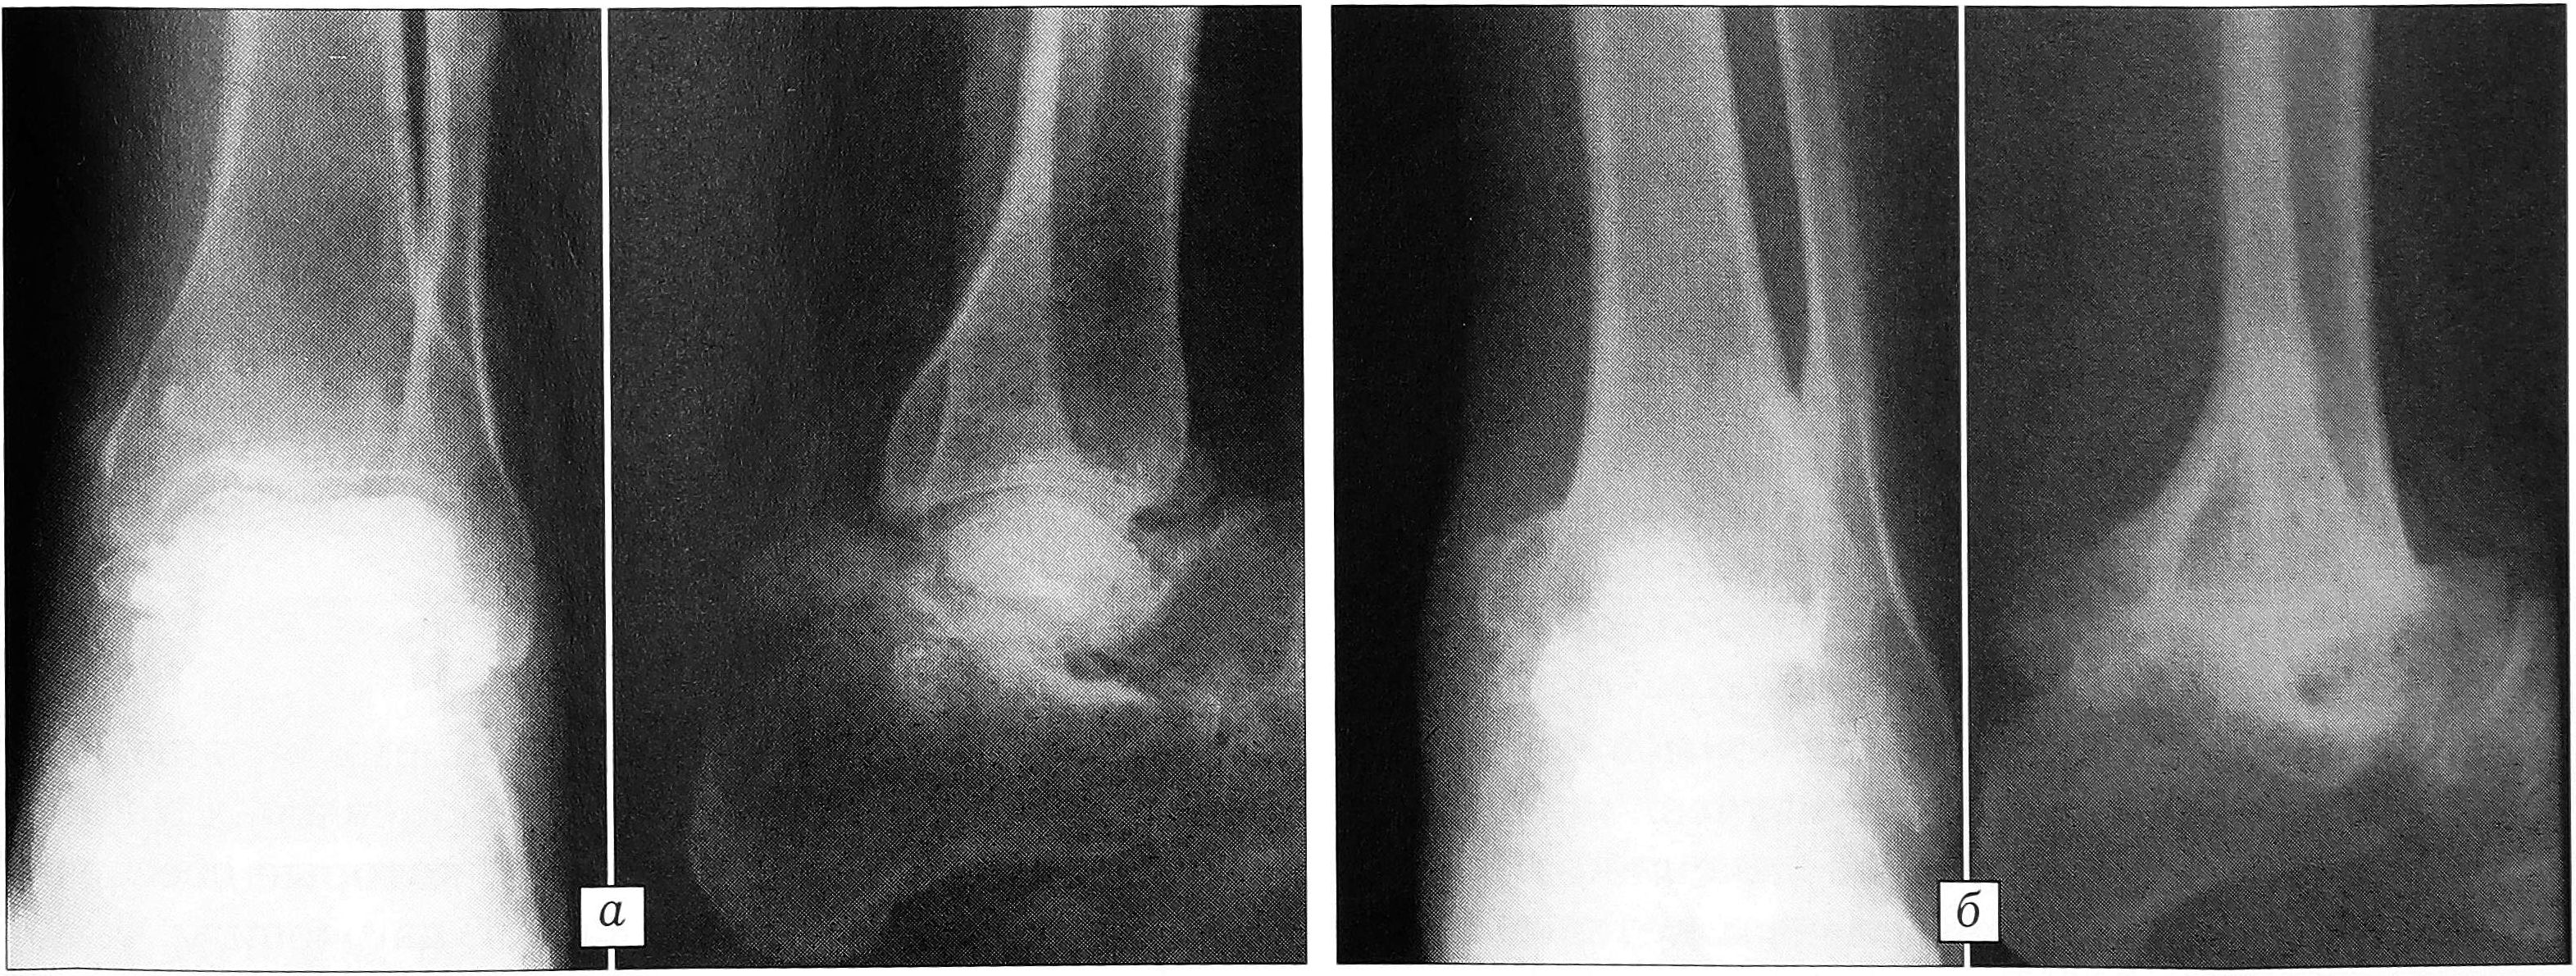

Пример 4. Больной С., 38 лет, был сбит автобусом. Госпитализирован в районную больницу с диагнозом: автодорожная политравма — открытая черепно-мозговая травма, ушиб головного мозга; закрытый подтаранный вывих левой стопы. Выписан на амбулаторное лечение через неделю (нарушение режима). Устранения вывиха стопы не производилось. Обратился в клинику через 1,5 года после травмы для определения степени инвалидности и уточнения показаний к ампутации левой стопы. Диагноз при госпитализации: асептический некроз блока таранной кости, деформирующий артроз левого подтаранного сустава, застарелый подтаранный вывих стопы, болевой синдром, лимфостаз левой стопы и голени (рис. 4, а). Произведены резекция блока таранной кости, компрессионный артродез (аппарат Илизарова). Разрешена нагрузка на ногу. Через 2 мес аппарат снят, наложен гипсовый сапожок с каблуком. Контрольный осмотр через 6 мес после операции: артродез состоялся, болей и отеков нет (рис. 4, б). В настоящее время работает сторожем, инвалид III группы.

Рис. 4. Рентгенограммы больного С. а — при поступлении (через 1,5 года после травмы); б — через 6 мес после операции.

Техника резекционной астрагалэктомии с оставлением кровоснабжаемой части таранной кости позволяет сохранить один из важных элементов рессорности стопы (таранно-ладьевидный сустав) в условиях анкилозирования зон над- и подтаранных суставов. Мы считаем целесообразным применение органосохраняющей тактики и прибегаем к полной астрагалэктомии исключительно редко.